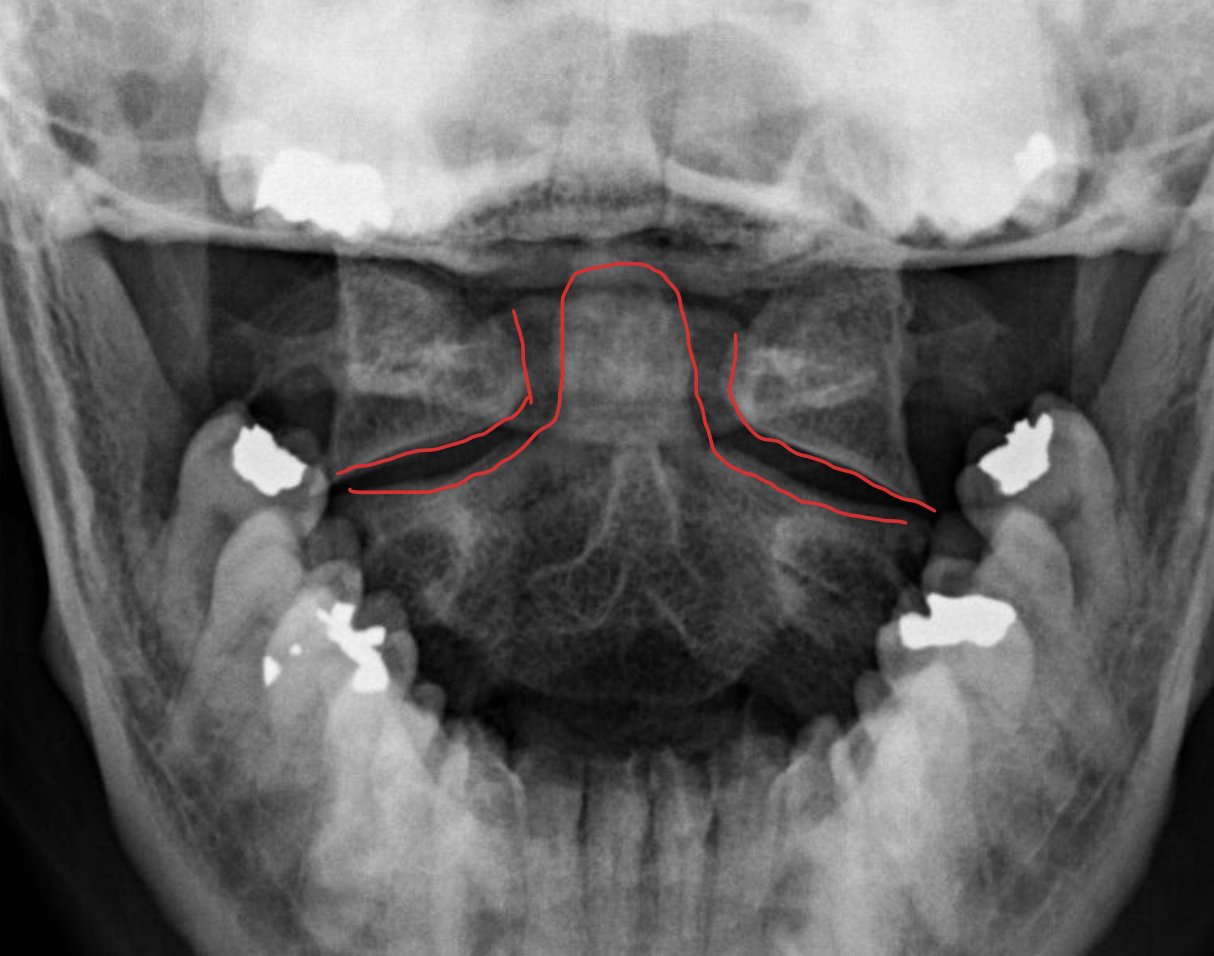

寰枢关节

Atlanto-axial